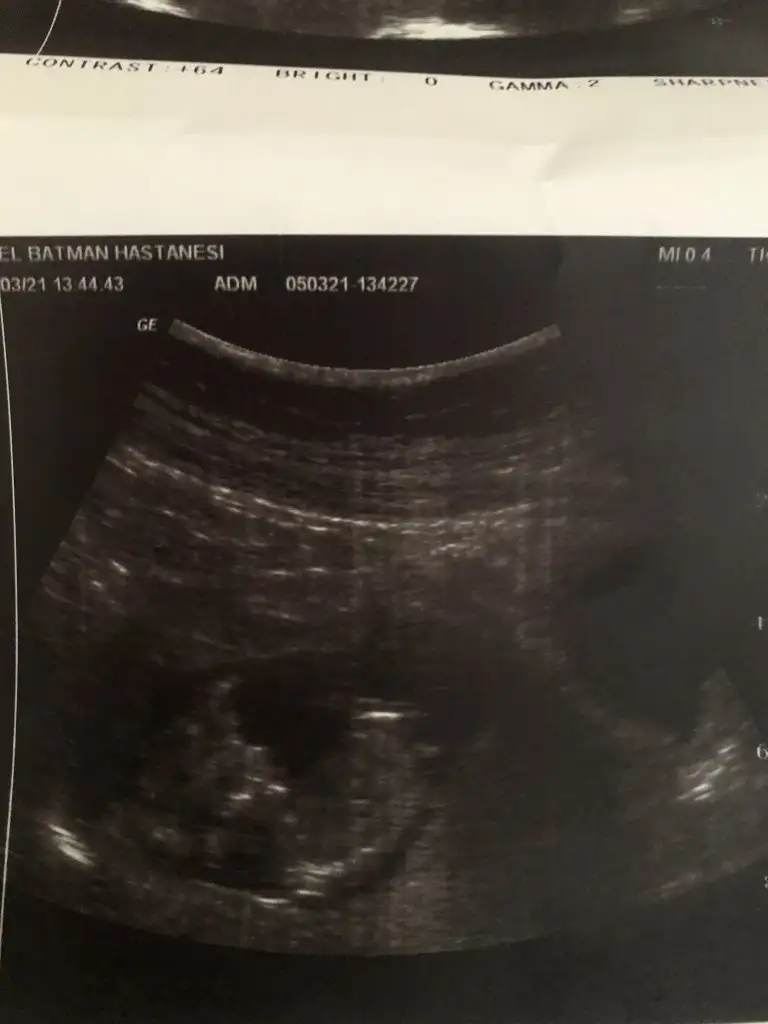

7 haftalik hamilelik bakarmisiniz lutfen 😍